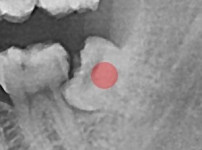

부분 매복 사랑니

조회

747

작성일

25-12-29